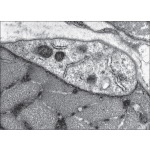

Electron Micrograph of a Satellite Cell In Adult Skeletal Muscle